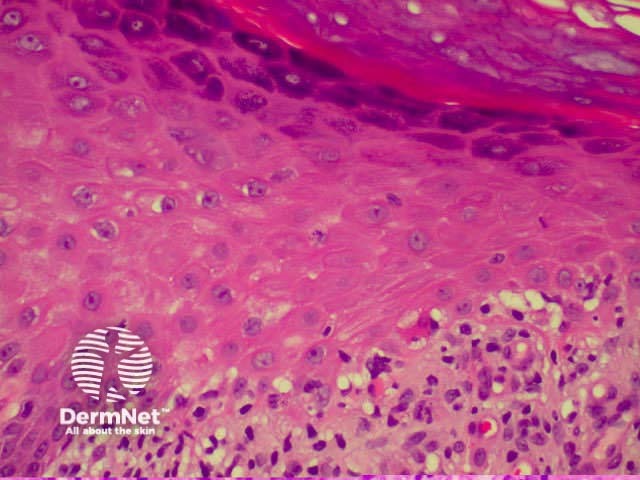

Lichen planus is the idiopathic version of a group of lichenoid disorders characterised by scaling papules or plaques. Link to a clinical description of lichen planus.

The histological features of lichen planus are:

The majority of lymphocytes in the often dense infiltrate are memory cells, identified using histochemistry by positive CD8 and CD45 RO markers.

Direct immunofluorescence nearly always reveals fibrinogen within the colloid bodies. Occasionally IgM and complement are also detected. The immunofluorescence pattern is not diagnostic as the same reactants can also be seen in systemic lupus erythematosus and erythema multiforme.

Lichen planus Lichen planus Lichen planus Lichen planus Lichen planus Lichenoid inflammation